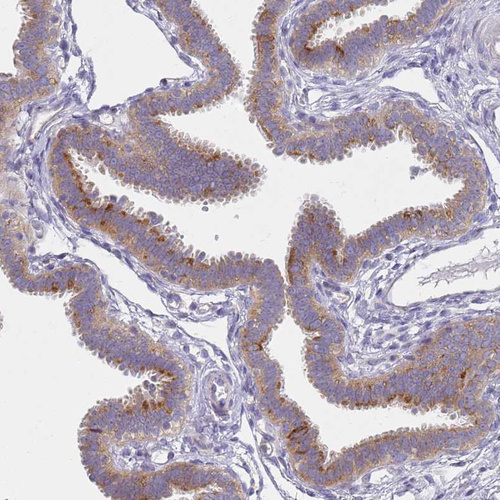

Immunohistochemical staining of human duodenum shows moderate cytoplasmic positivity in glandular cells.